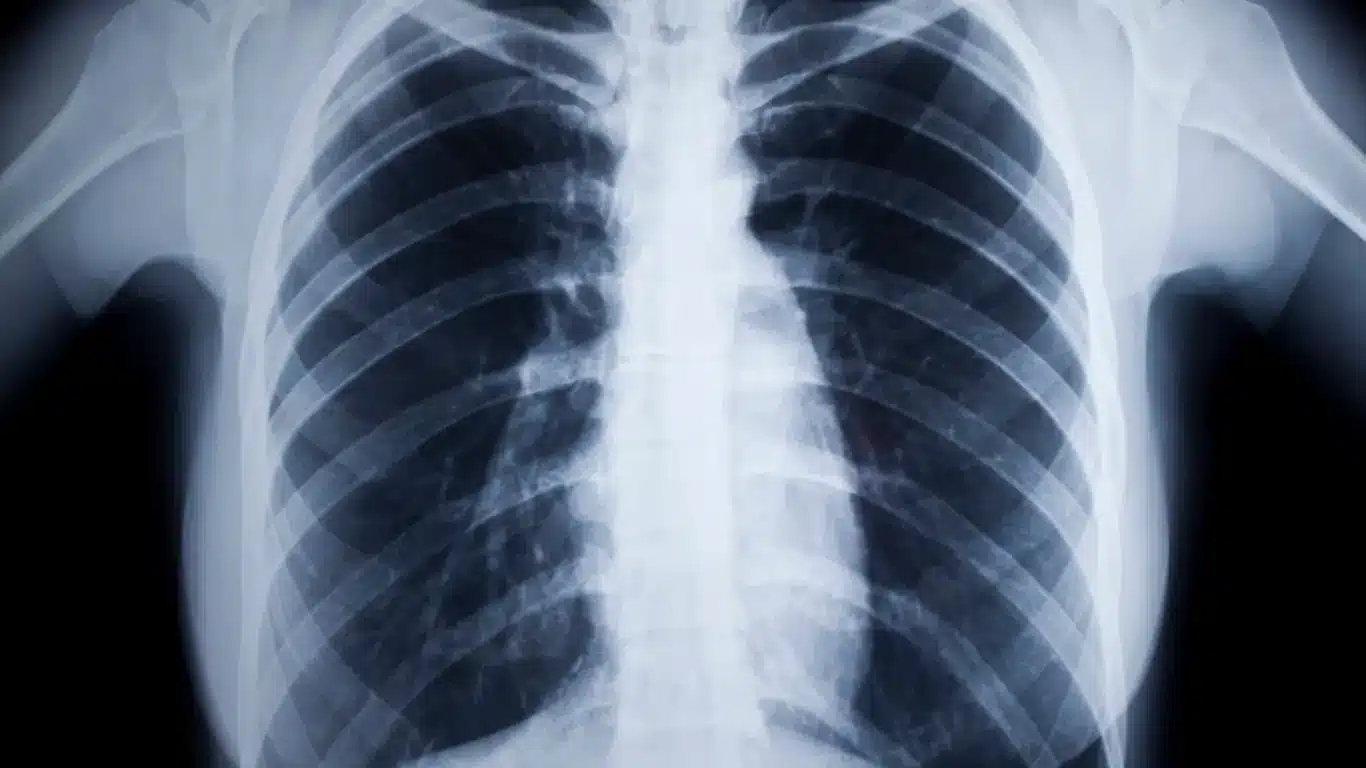

Vigilancia de salud con tecnología 100% digital. Especializados en tele-tórax bajo estándar OIT para detección de neumoconiosis y patologías de columna, garantizando resultados válidos para IESS y MSP.

Análisis estratégico sobre Rayos X Digital. Impacto y perspectivas.